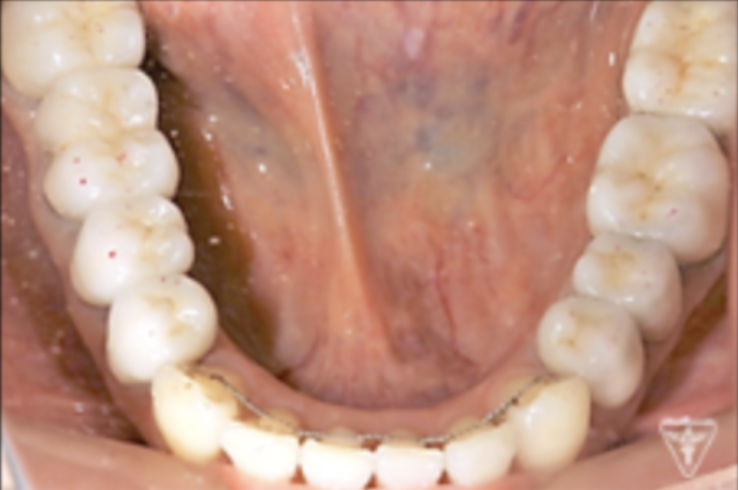

治療後

治療前後の比較